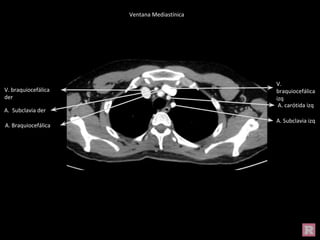

Ventana Mediastínica

Esternón

Escápula

V.

braquiocefálica

izq

V. braquiocefálica

der

A. carótida izq

A. Subclavia izq

A. Braquiocefálica

A. Subclavia der

Lóbulo superior

Esófago